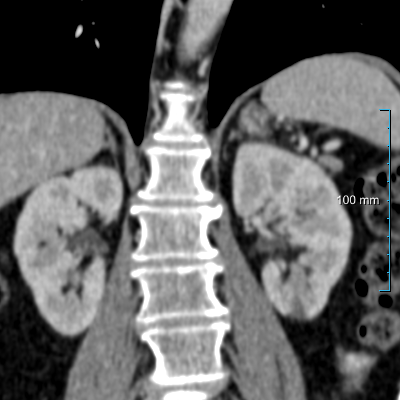

In this study, we propose an automatic method for segmenting the kidney parenchyma and kidney abnormalities in thorax-abdomen CT scans and compare it with the nnUNet. We trained our method on 215 thorax-abdomen CT scans and tested on additional 50 scans; the dataset consisted of scans from patients undergoing oncological workup. The dataset contains patients at different stages of disease and therefore abnormalities can be present in multiple body regions.

The dataset used in this study was collected from the Radboud University Medical Center, Nijmegen, the Netherlands. We randomly retrieved 1905 studies from 929 patients referred by the oncology department in a 12 month period. These patients did not opt-out for use of their data for research, Protected health information was removed from the DICOM data. This retrospective study was approved by the medical-ethical review board of the hospital. CT scanners from two manufacturers were used to acquire the CT scans: Toshiba (Aquilion One) and Siemens (Sensation 16, Sensation 64, and Somatom Definition AS). The reconstruction kernels were FC09, FC09-H, B30f, B30fs, and I30f. The slice thickness ranged from 0.5 to 3 millimeters, 90% of them between 1 and 2 mm. Severe abnormalities throughout the body are present in this dataset resulting from disseminated disease, surgery, chemotherapy, radiotherapy, etc.

We employed a radiology report analysis to curate a dataset of 138 clinical studies from 138 patients with kidney abnormalities, including cysts, lesions, masses, metastases, or tumors. We excluded six patients with unusual anatomy, three patients who had received kidney transplants, two patients with kidneys of irregular size, and one patient with a horseshoe kidney. The inclusion and exclusion criteria gave us 132 cases for analysis, which were then balanced with additional 133 random patient studies without kidney abnormalities, for a total of 265 CT scans from 265 patients. The patient cohort contains 56% males; the average age was 60 years, and the age ranged from 22 to 84. We divided this set into 215 CT scans for training (dataset A) and 50 for testing (dataset B). The test set was further subdivided, with 60% (30/50) containing abnormalities (dataset B30) and the remaining 40% (20/50) devoid of abnormalities (dataset B20). The distribution of the five types of abnormalities (tumors, cysts, masses, lesions, and metastases) was proportional among the 30 cases in dataset B30 (six cases per abnormality), which were randomly selected.